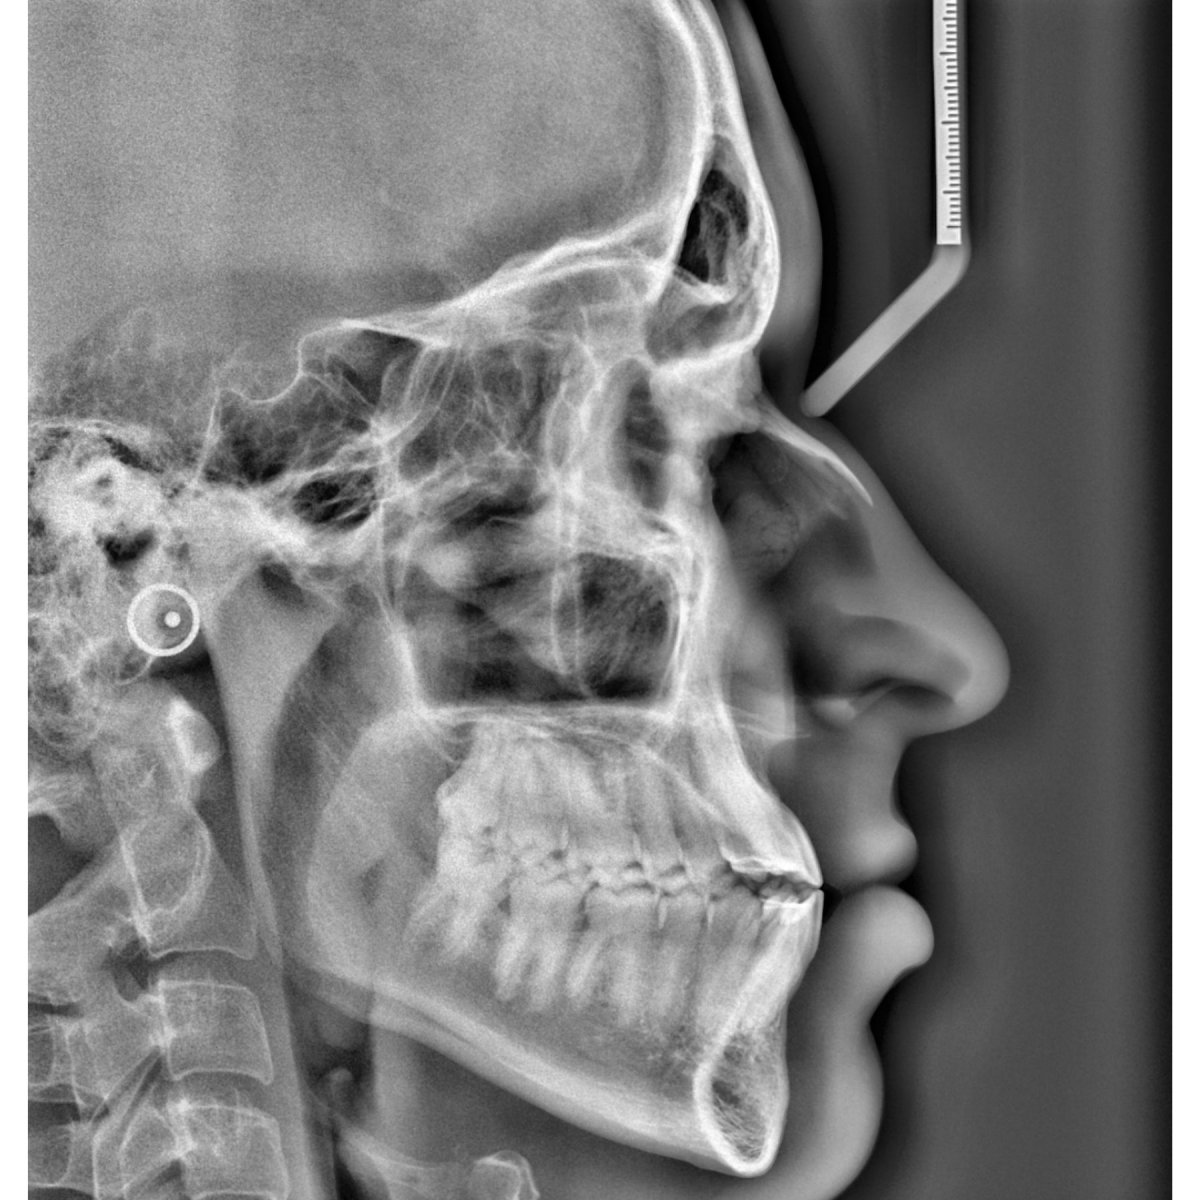

La physiothérapie maxillo-faciale correspond à la physiothérapie qui s’occupe des troubles et symptômes liés à l’articulation temporo-mandibulaire, la mâchoire, la bouche, le crâne, la face et le cou.

Chirurgie orthographique - Fiche d'éducation thérapeutique

Retrouver le feuille d'éducation thérapeutique concernant la chirurgie orthographique sur le blog de CapRol.

- Quelques définitions

- Objectif d'une chirurgie orthographique